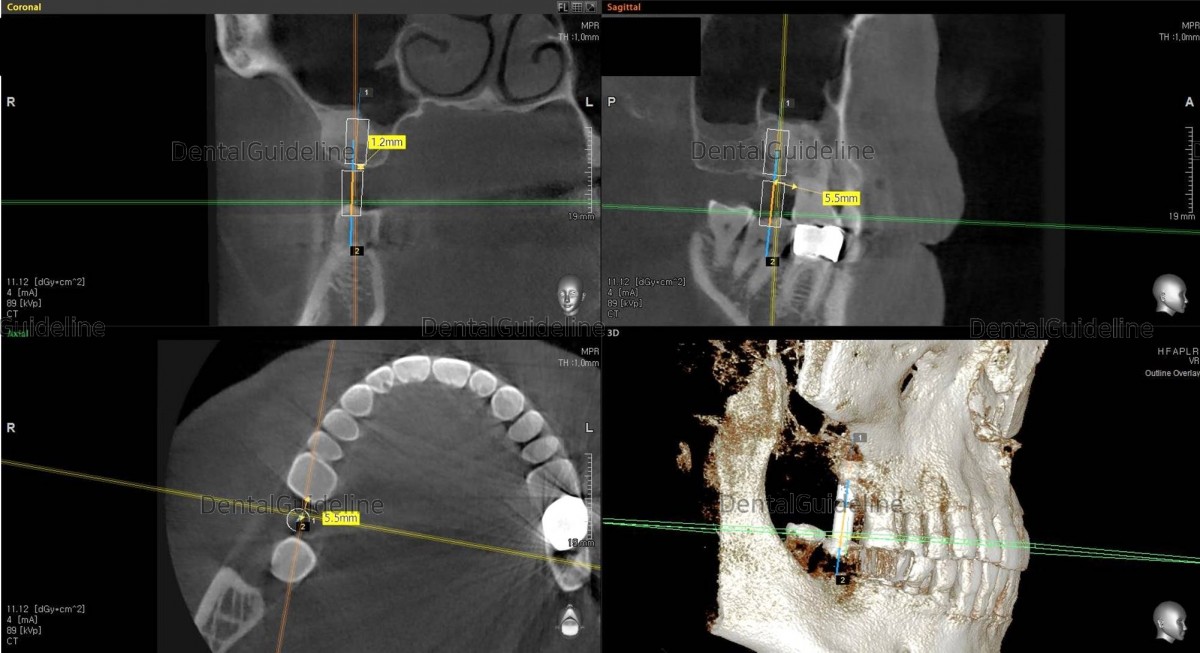

Simply simulated to find the optimal diameter and length of the implant